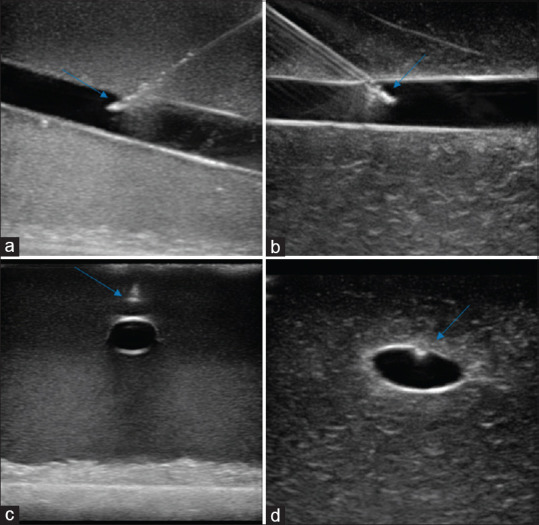

Methods: This was a randomized crossover study conducted at a tertiary care hospital of India. The aim of the study was to develop a prototype low-cost gelatin-based vascular phantom and compare it with a commercially available phantom. Gelatin, psyllium husk, corn starch, antiseptic liquid, food-coloring agent, latex balloons, and metallic containers were used to prepare the gelatin phantom. The newly prepared gelatin model was labeled "Model A" and the commercially available gelatin model was labeled "Model B." Emergency medicine residents (n = 34) who routinely perform ultrasound (USG)-guided invasive procedures were asked to demonstrate USG-guided in-plane and out-of-plane approach of needle-tracking in both the models and fill out a questionnaire on a Likert scale (1-5). An independent supervisor assessed the image quality.

Results: The cost of our phantom was USD 6-8 (vs. USD 1000-1200 for commercial phantom). The participants rated the ease of performance and tissue resemblance as 4 (interquartile range [IQR]: 4-5) for both the models "A" and "B." The supervisor rated the overall performance as 4 (IQR: 3-4) for both the models. In all the parameters assessed, model A was noninferior to model B.